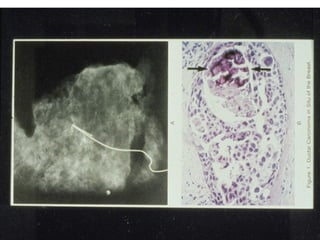

• Mammogram:

– The most common method of detection is by

identifying mammographic calcifications

– The calcifications may be linear and

branching...following the lumens of the

involved ducts

Mammography showing a normal breast (left) and a cancerous breast

(right).

Linear and

branching

calcifications

Grossly

visible

comedo

necrosis